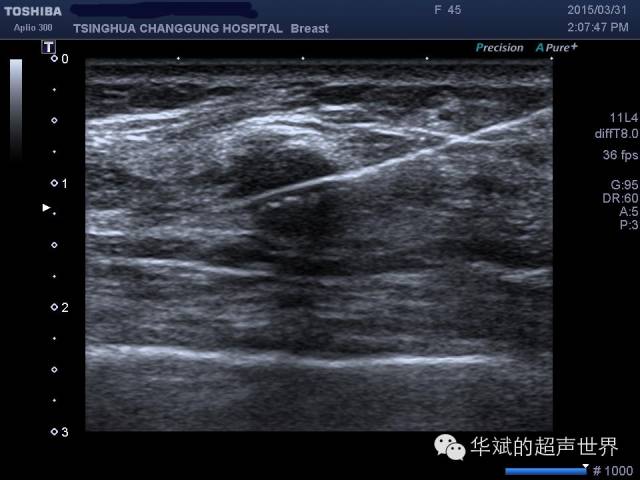

“枪刺征”,枪刺征实际上是一种声速失真伪像。

超声在不同组织中的传播速度不同,就会造成后方的结构的轮廓出现变形扭曲。

穿刺针在穿过不同组织和病变时,由于不同组织和病变的的的声速差别,会造成穿刺针扭曲的现象,呈现所谓的“枪刺”征。

图 乳腺低回声肿物穿刺,由于肿物内的声速高于周围组织中的声速,因此,穿刺针显示为向前移位,类似“枪刺”,是为枪刺征。